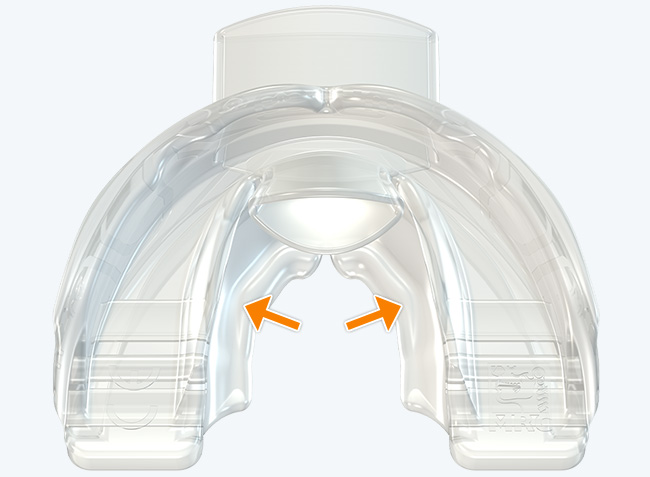

The Myosa® for TMJBDS® S1H is specifically designed for patients who are breathing and disordered sleep (BDS) primary with moderate to severe BDS as indicated by a Breath Hold Time (BHT) of 20 or less. These patients may or may not have TMJ disorders, but due to the severity of their BDS, they require immediate improvement of their airway. The features of the appliance not only work to open the airway, but also allow patients to undertake initial exercising of the lip, tongue and airway muscles. Progress to the S1 when the patient’s BHT reaches 20 seconds or more.